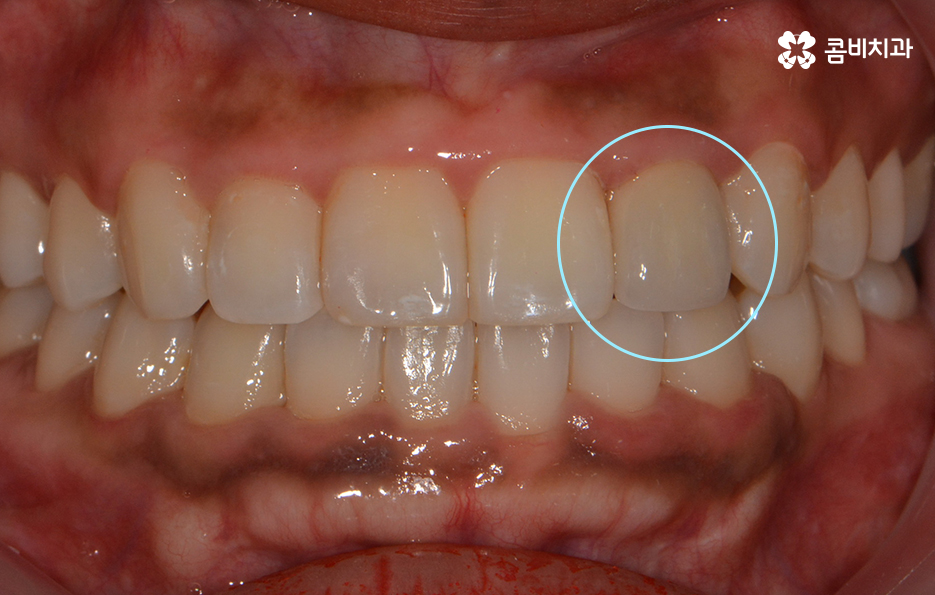

마지막으로 소개드릴 앞니 충치치료 방법은 라미네이트입니다.

충치가 앞니에 발생했을 때 초기에는 레진으로

치료를 하지만 손상이 좀 더 심한 경우 라미네이트를 활용합니다.

라미네이트는 충치 치료 방법보다는 빠른 치아성형 방법으로

많이 알려져 있는데 앞니의 벌어짐, 깨짐 등의 치료에도 많이 쓰입니다.

심미성이 우수하지만 치아의 겉면에 세라믹 박편을

붙이는 방식의 치료 방법이기 때문에

자연치아에 비해 내구성이 약한 편이므로

음식물을 섭취할 때 주의를 하시는 것이 필요합니다.

위 환자분의 경우 기존에 타 치과에서 치료받으셨던

라미네이트가 깨져서 내원하셨습니다.